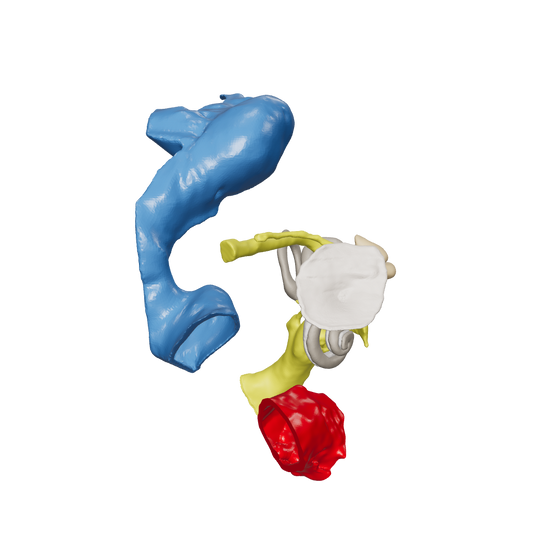

Dissect each one to learn human temporal bone anatomy, hearing and vestibular systems.

*High Contrast Colors* 3D Temporal Bones to Introduce Anatomy (6-pack)

Regular price $402.00 USDRegular priceUnit price per -